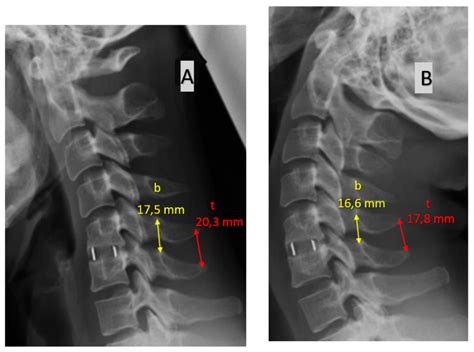

ℹ️ Note: Regular follow-up appointments are vital. Your surgeon will likely take X-rays at various intervals to track the progress of the bone fusion and ensure the hardware remains correctly positioned.